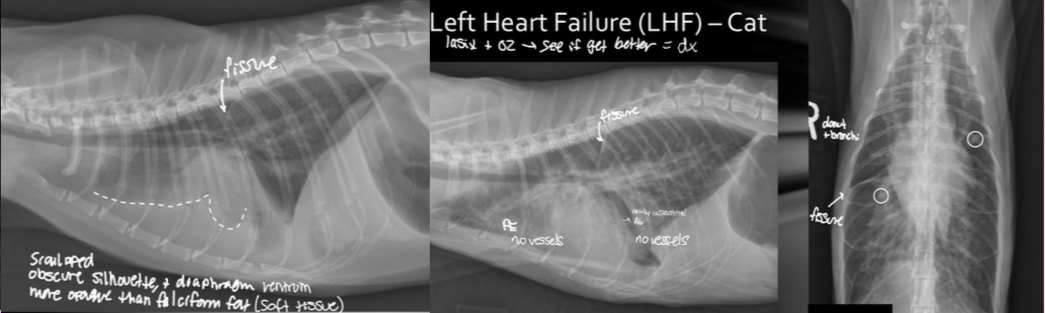

Cat- what sided heart failure

LHF

What features of this image screams this cat is in LHF

Pleural effusion

-scalloping and fissure lines present

-vessels are not traceable in cr.ventral thorax

Cat- what kind of heart failure is happening

What 4 patterns can cats have when LHF and where is it distributed

-unstructured interstitial

-alveolar

-bronchial

-pleural effusion

-distributed everywhere and anywhere

What are the 2 features of pleural effusion that help you differentiate it from other patterns?

-fissures lines with lungs

-no vessels can be traced